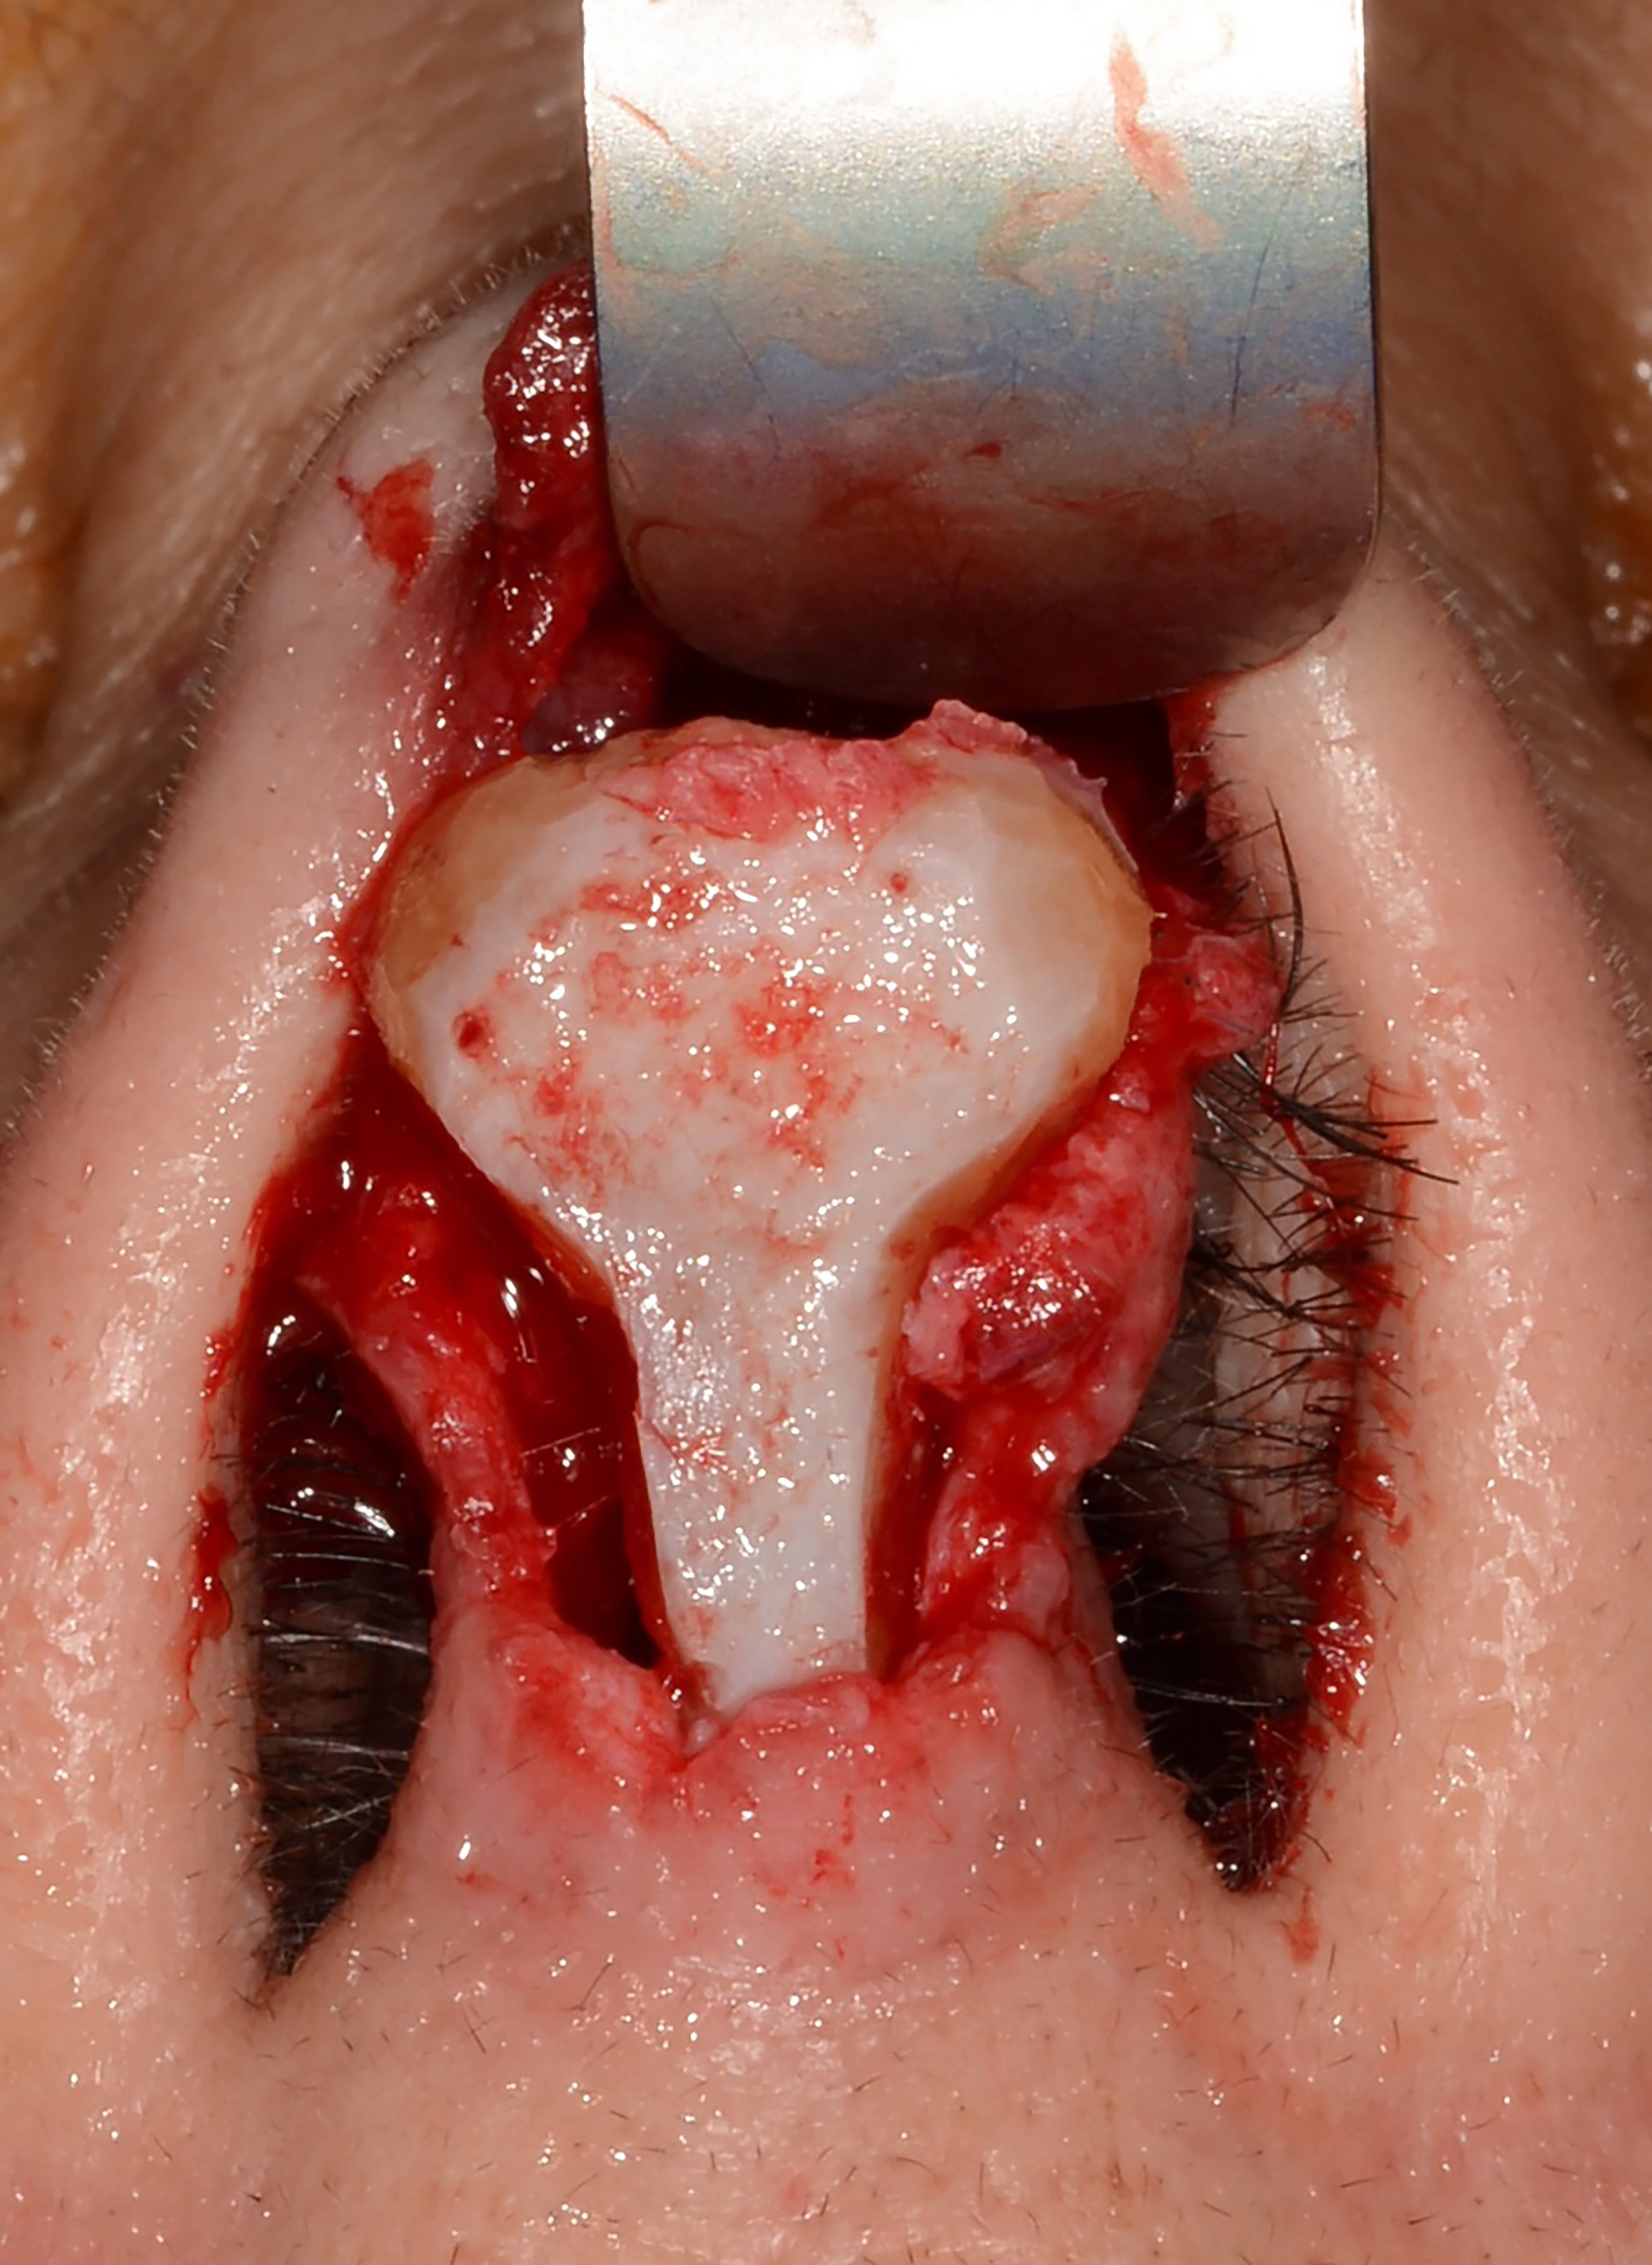

Lateral wall batten

The lateral wall batten is one of the most common grafting techniques in functional rhinoplasty. It is used to address dynamic internal and external nasal valve collapse and can be placed with either an endonasal or open approach. A septal or conchal cartilage graft is positioned at the center of collapse during inspiration, usually at the intervalve area of the nose. The graft is placed in a submucosal pocket superficial to the alar cartilage and secured with a through-and-through suture to collapse any existing dead space. It is important that the graft rests laterally at the bony piriform aperture. The graft should be slightly convex to help pull the side wall laterally [Figures 3 and 4]. Cosmetically, this grafting technique will widen the lateral nasal wall.